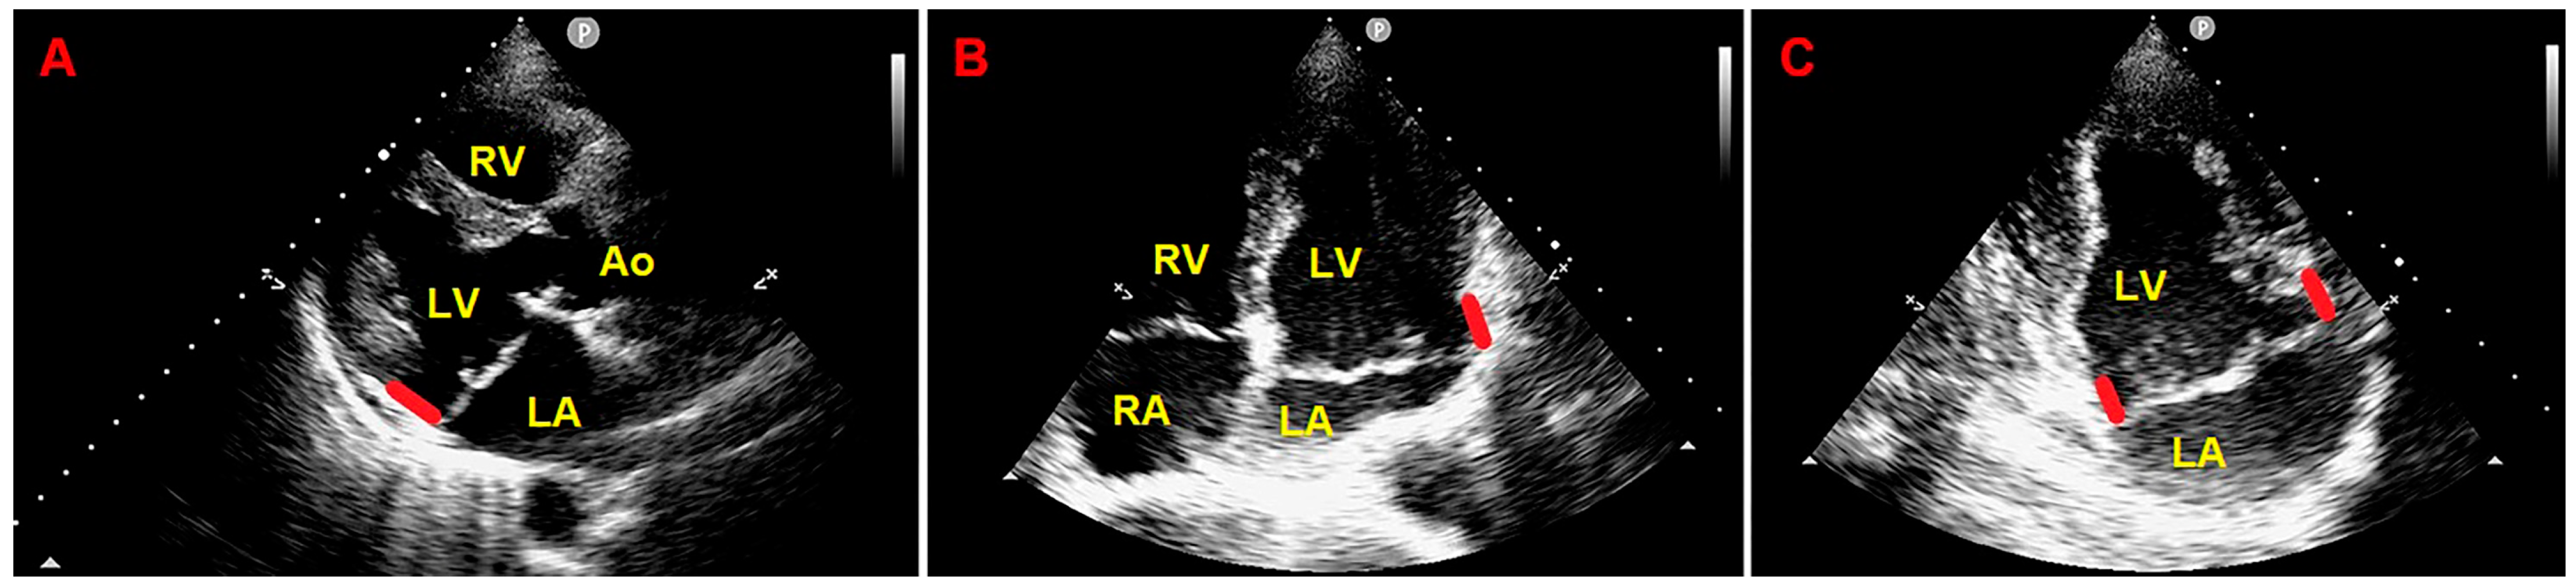

2. Clinical Case

3.2. The Role of Echocardiographic Techniques in MAD Assessment